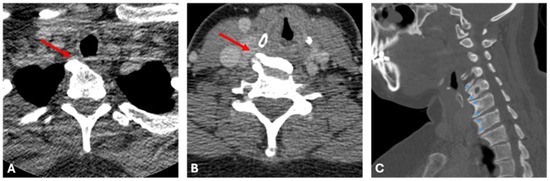

2.2. Case B